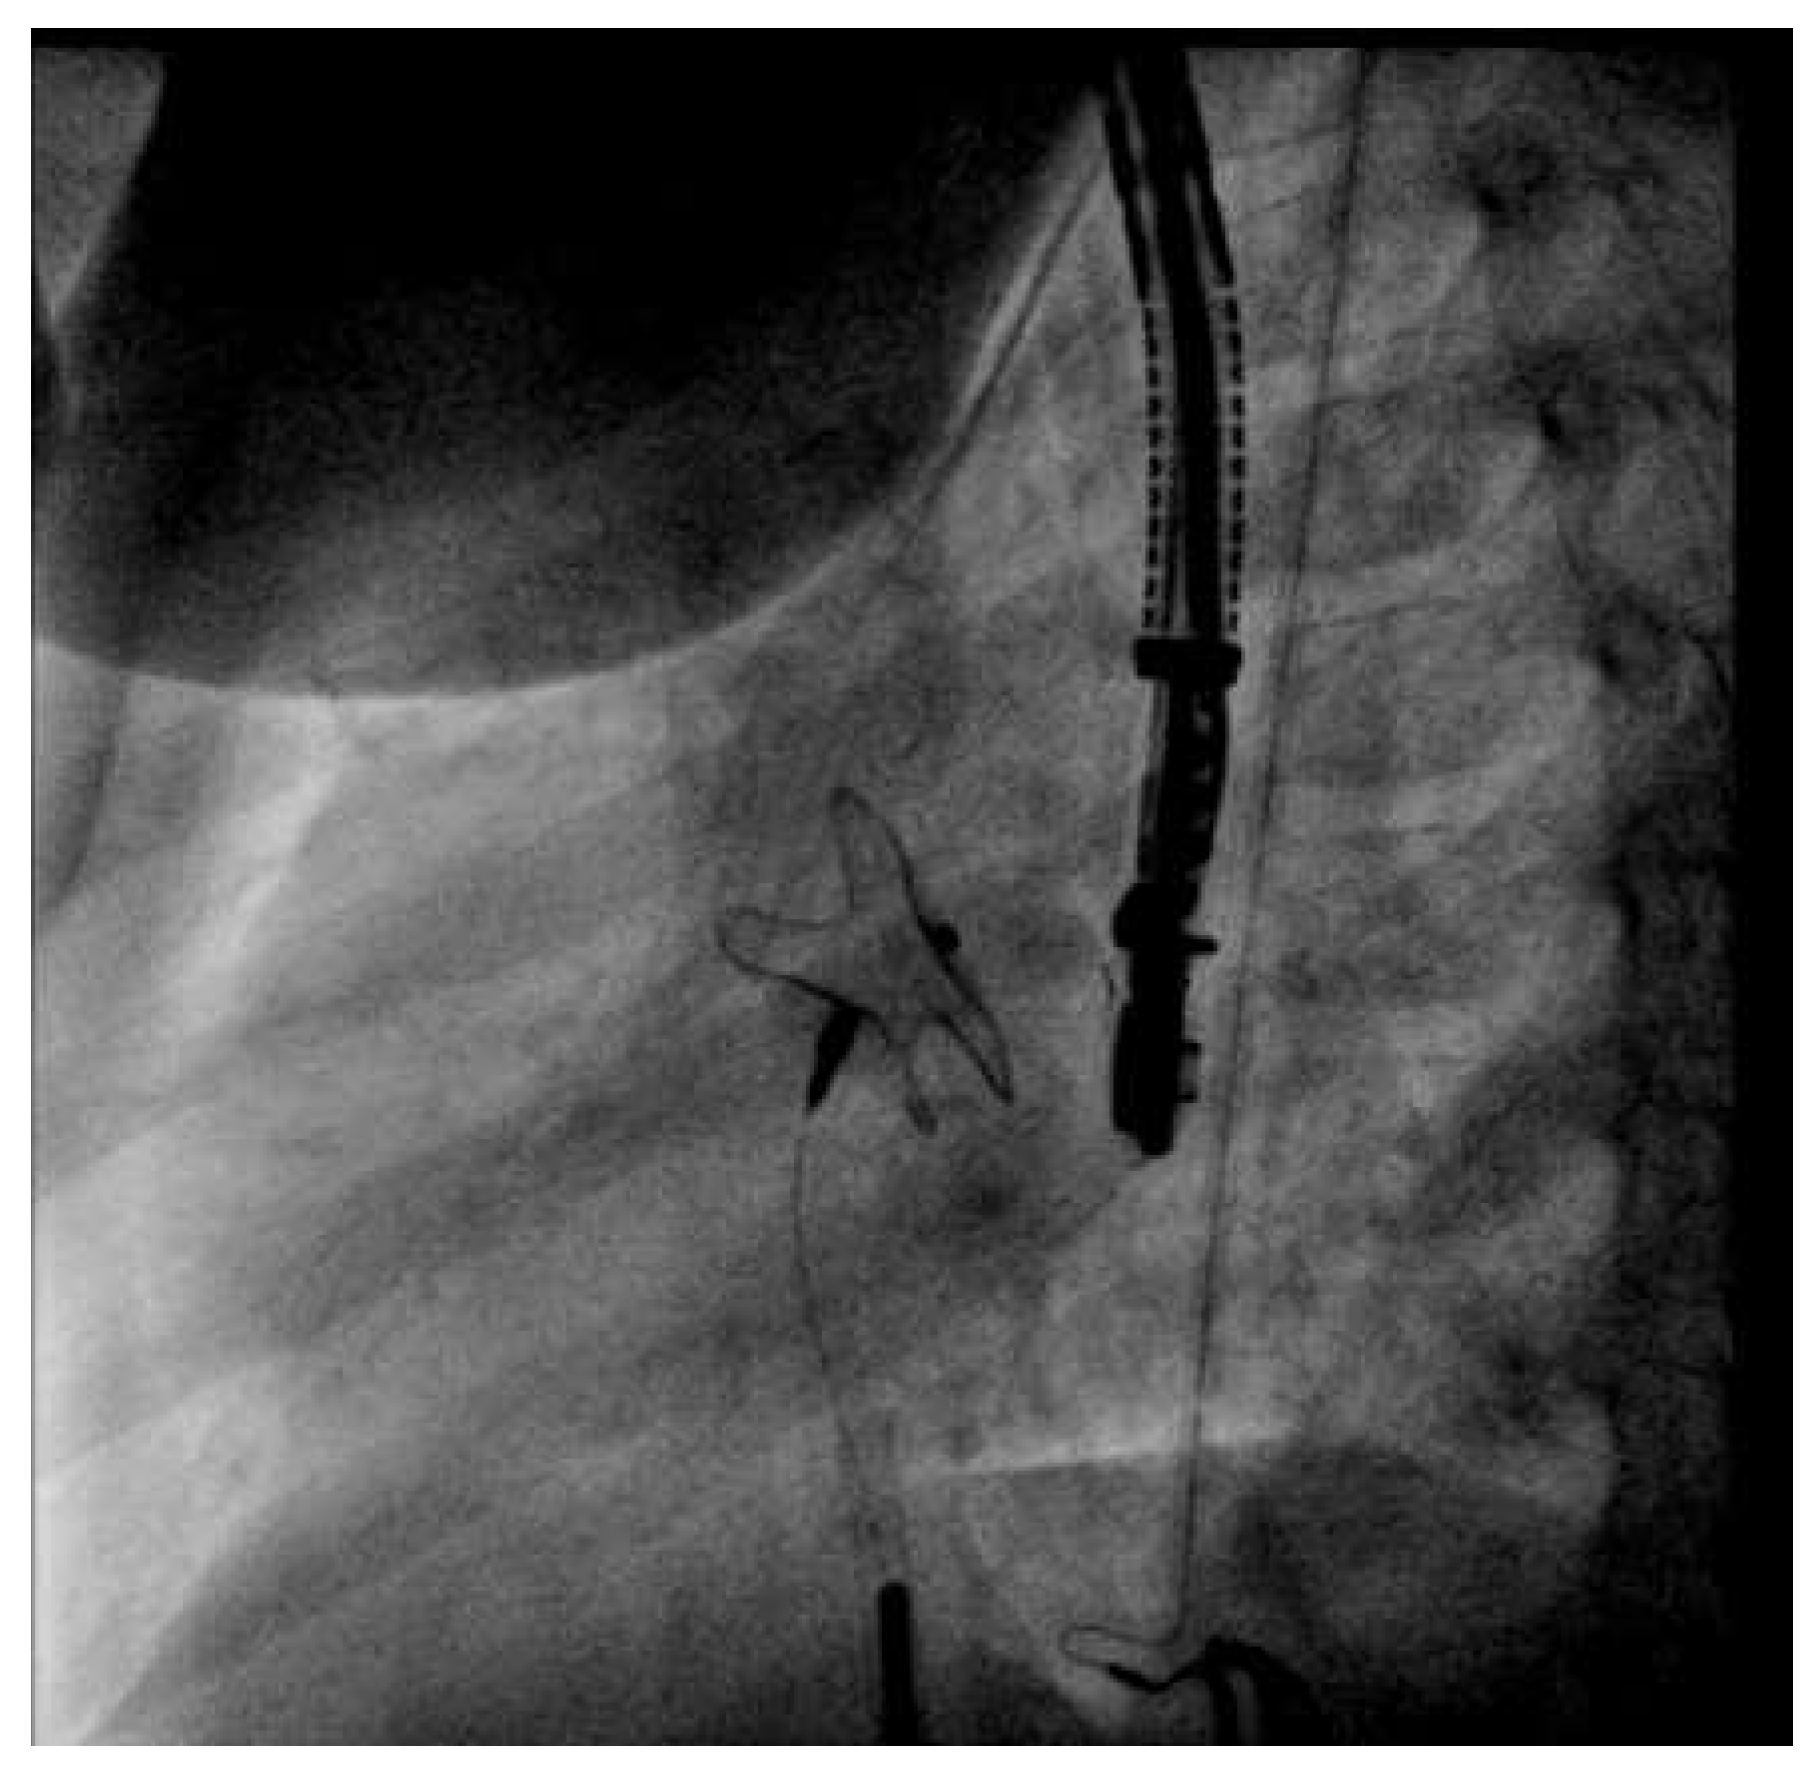

The procedure was conducted under general anaesthesia and fluoroscopic guidance combined with transoesophageal echocardiography monitoring. Aher tracheal intubation, venous access was gained through the right femoral vein with a 6 French CheckFlow introducer set and the patient was treated with 1 000 units of intravenous unfractionated heparin and 900 mg of intravenous cefuroxime. The atrial defect was passed under fluoroscopic guidance with a 4 French multipurpose catheter. A stiff guidewire was placed in the leh superior pulmonary vein. A 14-mm Hyperion Atrial Septal occluder (Comed) was chosen on the basis of the findings of echocardiography and balloon sizing (24-mm Amplatzer sizing balloon, St. Jude Medical, Plymouth, USA). We decided to close the defect with 14-mm Hyperion Atrial Septal Occluder (Comed). The 6 French introducer sheath was exchanged for a 10 French delivery Hyperion sheath (Comed) and advanced into the leh atrium. The preassembled Hyperion occluder was loaded and the leh atrial disc of the occluder was opened. Aherwards, the delivery sheath and the disc were retracted as a unit until the disc hugged the septum. Subsequently, the right atrial disc was opened in the right atrium. At this stage, the HyperionFlexPusher cable allowed for retraction of its stiff sleeve with the device remaining attached to the screw at the end of the core wire. This relieves the distortion by relaxing the tension of the system. The device position achieved came close to the final position with the precise orientation to the atrial septum (Figure 1, video 1). At this point, the device could still be retrieved and redeployed or replaced. The device was then released by counterclockwise torquing the core wire (Figure 2, video 2). Ideally, the stiff sleeve should be readvanced at least partially before that to avoid entangling of the flexible core wire during torquing. The patient was discharged on the following day aher a TTE and chest X-ray had confirmed good device position. Acetylsalicylic acid (100 mg per day) was recommended for 6 months.

Figure 1. Video 1. HyperionFlexPusher Cable with 14-mm Hyperion Occluder in position before releasing (left anterior oblique 72° / caudal 12° projection).